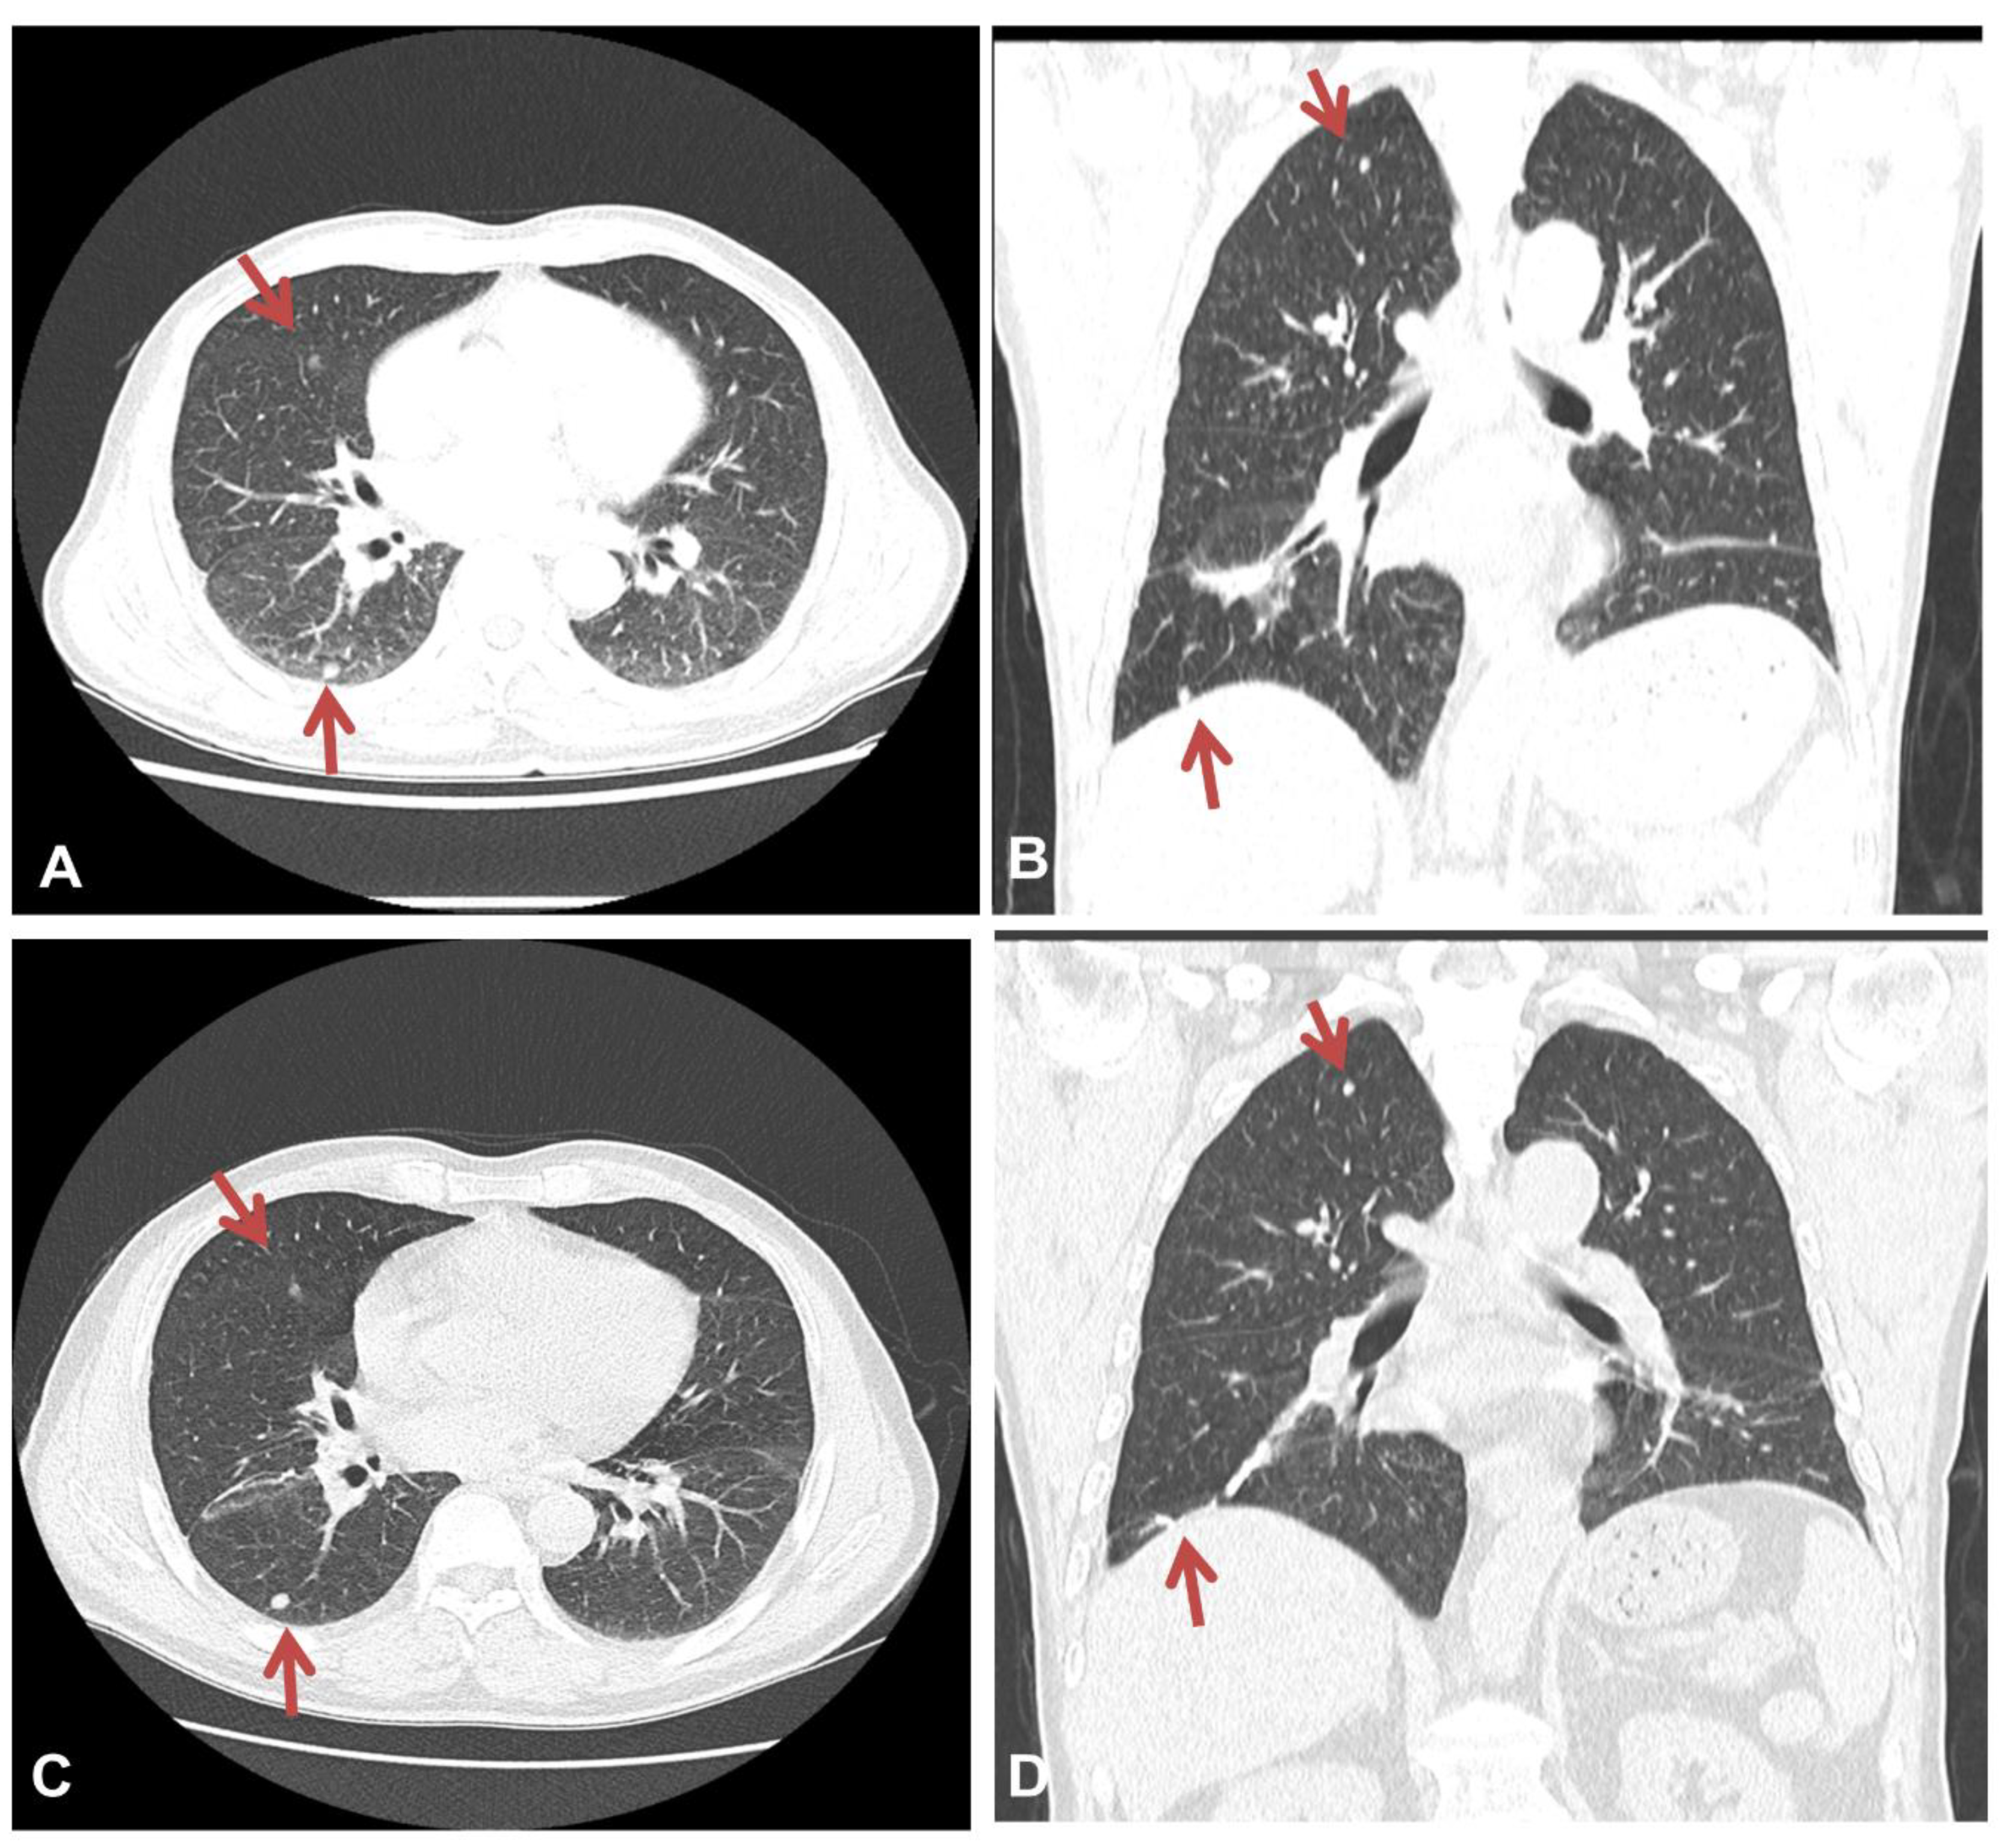

At admission, physical examinations showed no abnormal findings. The patient’s initial vital signs were as follows: blood pressure, 138/84 mmHg; body temperature, 36.3 °C; pulse rate, 92 beats/min; and respiratory rate, 20 times/min. The initial arterial blood gas analysis revealed a pH of 7.416, PaCO2 of 37.8 mmHg, PaO2 of 67 mmHg, and SaO2 of 93.0% (room air). Laboratory results revealed an increase in the serum levels of C-reactive protein (6.1 mg/dL), while other laboratory findings were within their normal limits. Chest X-ray imaging revealed features of bilateral nodular opacities with lung nodules and pleural thickening compared to a previous chest X-ray 12 years prior (Figure 1A,B). Enhanced chest CT showed multiple well-defined nodules in both lungs and a 4.1 cm peribronchial consolidation with fibrotic changes in the right lower lobe (Figure 2A,B). Empirical antibiotics (gemifloxacin 200 mg every 24 h) were introduced after bacterial cultures were obtained because bacterial bronchitis or organized pneumonia could not be ruled out based on symptoms of dyspnea, cough, and purulent sputum.

A follow-up chest CT scan performed at 3 and 12 months after the diagnosis of asbestosis showed no interval changes, with multiple well-defined nodules remaining apparent in both lungs (Figure 2C,D). The patient is currently undergoing outpatient visits with no significant changes.

Figure 2. Chest CT findings at admission and 12 months after the diagnosis of asbestosis. Chest CT imaging revealed multiple well-defined nodules in both lungs (A) and a 4.1 cm peribronchial consolidation with fibrotic changes in the right lower lobe (B). There was no significant interval change in the multiple lung nodules on a chest CT scan taken 12 months after the diagnosis of asbestosis (C,D). The red arrows indicate lung nodules.